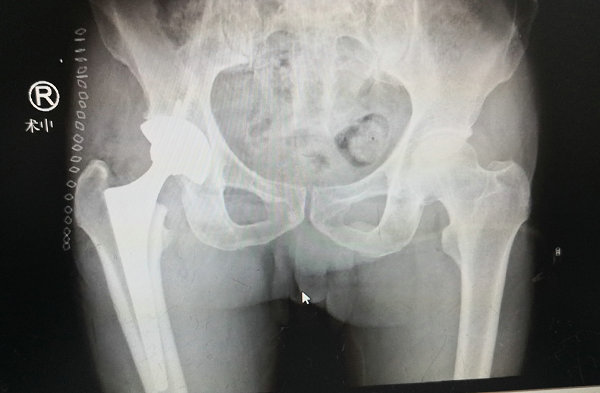

两天后,张贯林副院长和蒋主任共同为患者进行了髋关节置换手术,术中,手术医生如“庖丁解牛”,轻车熟路,凭借娴熟的技术,成功完成手术。 “简单地说,就是手术完全基于自然解剖间隙,不切断任何肌肉或肌腱,完整保留了外旋肌群和关节囊。患者采用平卧或侧卧位,手术医生可以更准确地放置假体,降低了术后髋关节脱位的风险。术后第一天患者即下床进行了锻炼,大大缩短了患者康复的时间,达到了真正意义上的微创效果,实现了‘快速康复’的理念。”蒋守海主任说。

术后

术后第一天,赵大爷就下地活动了。术后第二天开始练习下蹲,脱拐行走。术后一周,老人出院了。微创治疗后康复速度可见一斑。